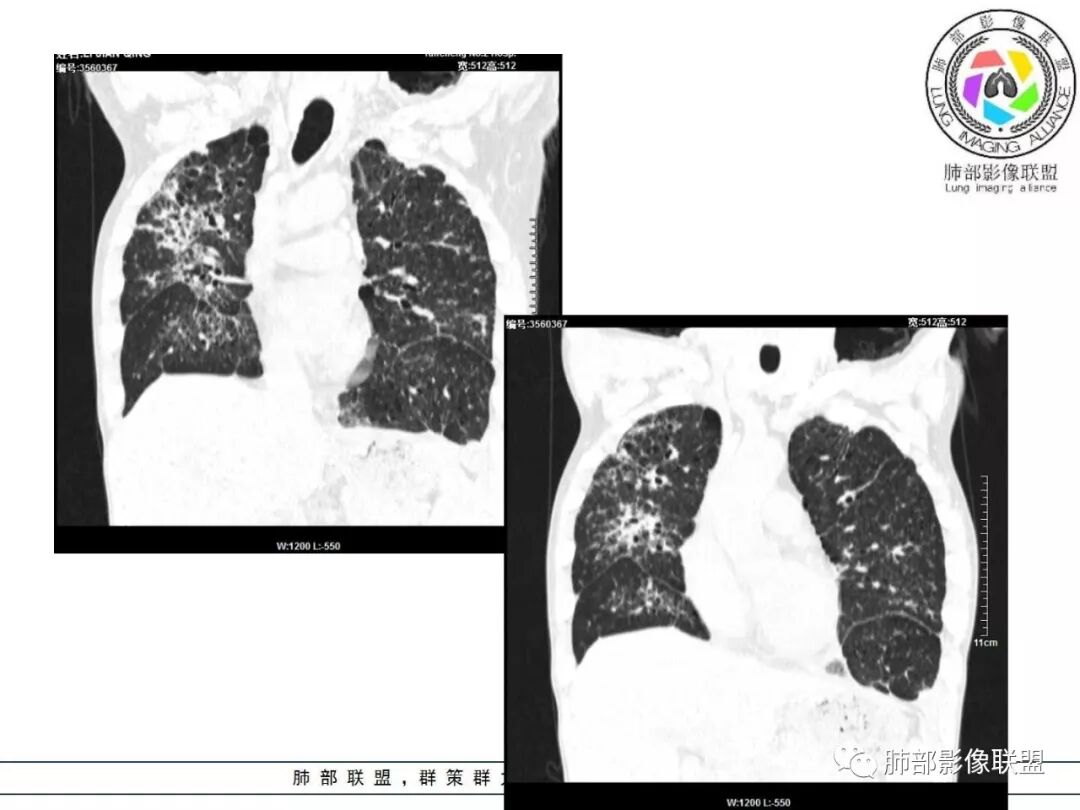

胸部CT:两肺弥漫病灶,磨玻璃影,少许实变,部分累及胸膜,磨玻璃区可见囊?少许胸腔积液,两肺可见结节,支气管血管束增粗,小叶间隔增厚,支气管走形有扭曲扩张,可见纤维化。气肿、大泡。考虑:感染性病变,PCP?查下HIV,CD4,G等。鉴别结核、结缔组织病肺浸润。

患者双上肺弥漫性改变,小叶间隔增厚,中央轴为主,胸膜下少量,感染为主,鉴别结核。

55多男性,发热为主诉,体温38℃-39℃多,午后及夜间发热为主,峰值40℃,伴黄痰,CRP高,血糖正常,胸部CT:两肺弥漫病灶,磨玻璃影,少许实变,部分累及胸膜,两肺可见结节,似可见树芽,支气管血管束增粗,小叶间隔增厚,见肺气肿、大泡。考虑感染性病娈,肺结核可能性大。

患者中年男性,发热1月,体温38℃-39℃,峰值40℃,无畏寒、寒战,伴黄痰,CRP升高明显,降钙素原稍升高,血沉、血糖正常。胸部CT:两肺弥漫病变,磨玻璃影+点片渗出,部分累及胸膜,磨玻璃区边界清楚,少许胸腔积液,两肺支气管血管束增粗,小叶间隔增厚,部分支气管走形有扭曲扩张,可见肺气肿、右肺尖肺大泡及部分纤维化改变。综合考虑:感染性病变。结核或PCP可能性大,鉴别风湿免疫、结缔组织疾病肺浸润和腺癌等恶性病变。

双肺弥漫性病变,多发磨玻璃密度及小叶间隔增厚,大部分沿支气管血管束分布,伴支气管轻度扩张,以午后及晚上发热为主,考虑感染性病变,间质性结核可能大,另双肺多发肺气囊,LIP待排

病变一般沿血管支气管束分布或小叶分布,一般上肺多于下肺(这与常见继发性肺结核分布相若)。

常会伴有其他继发性肺结核病灶,如斑片影、结节影,树芽征,新旧不等改变。

2. 肺气肿背景(小叶中心性肺气肿);双肺多发病灶整体沿血管支气管束及胸膜下分布,以上叶及下叶背段分布为主,有实变及GGO,边界清楚,有树芽,小叶间隔及中央间质增厚,叶间裂见到多发结节,部分支气管不规则牵拉扩张,提示病灶纤维化明显,结合临床病史,考虑病灶为间质性感染,肺门及纵隔内有钙化淋巴结,小叶间隔结节,考虑淋巴道增值性疾病可能,综合常规要怀疑间质性肺结核。